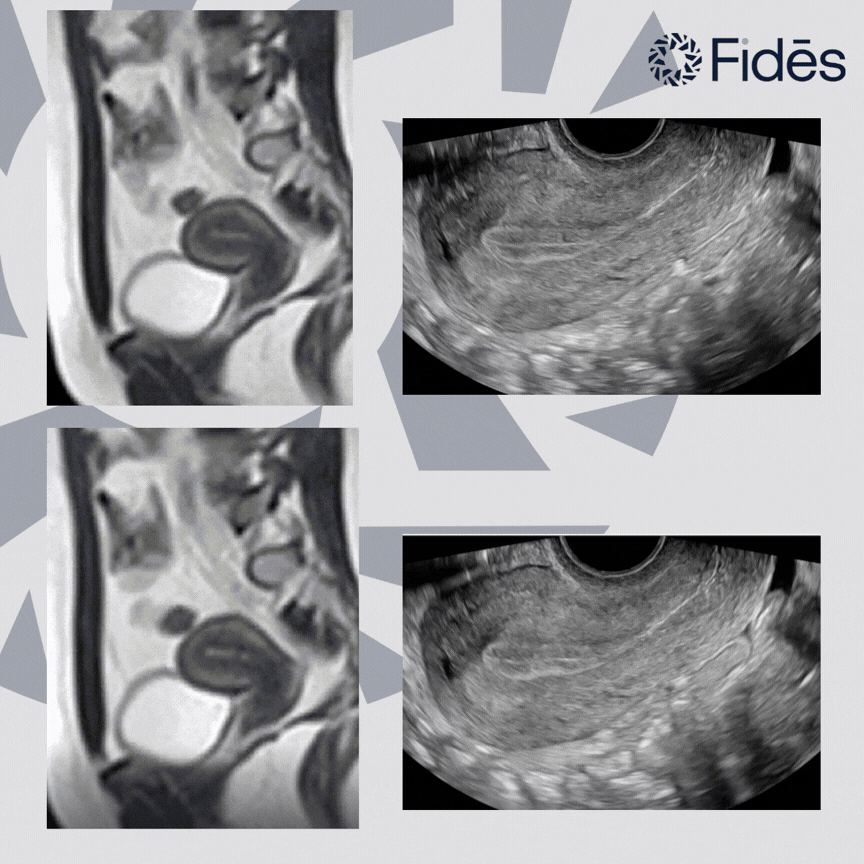

Standard imaging techniques still focus on static images and scores. These snapshots focus on structure, not function. Given that most drug development is concerned with function, it is clear that we’re missing a key dimension – movement.

Across the menstrual cycle, the uterus is dynamic, from menstruation (where we see fundocervical waves) through the follicular phase (involving cervico-fundal peristalsis) to the luteal phase (reduced peristalsis and changes in the direction of contractions) and finally ovulation (increased frequency and strength of contractions), to start the process again.

What Fidēs brings to clinical trials is unparalleled expertise in the evaluation and quantification of motion in organs, and can help with the design and delivery of high impact studies. Quantitative cine uterine imaging could finally move us beyond static snapshots to a true dynamic understanding.